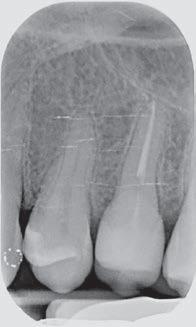

The canal was sealed with a Thermafil™ cone (Dentsply Sirona) with an apical diameter of 0.30 mm (Figs. 3-4).

glass fibre Figure 3: Root canal therapy completed under proper isolation. Figure 4: Radiography of completed root canal therapy and reconstruction made completely in glass hybrid cement. Figure 5: Clinical crown lengthening with a minimally invasive technique without mesial and distal discharges. Note the proximity of the reconstruction in glass hybrid material to the mesial bone ridge. Figure 6: Suture at the end of surgical therapy. It was left in place for 7 days Figure 7: Suture removal at 7 days. Post-surgical edema is still present.